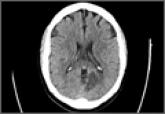

ArticleAtypical Acute Myocardial Infarction and Concomitant Acute Cerebral InfarctAuthor:Jenny Castillo, MDPublish date: July 5, 2016 Read More